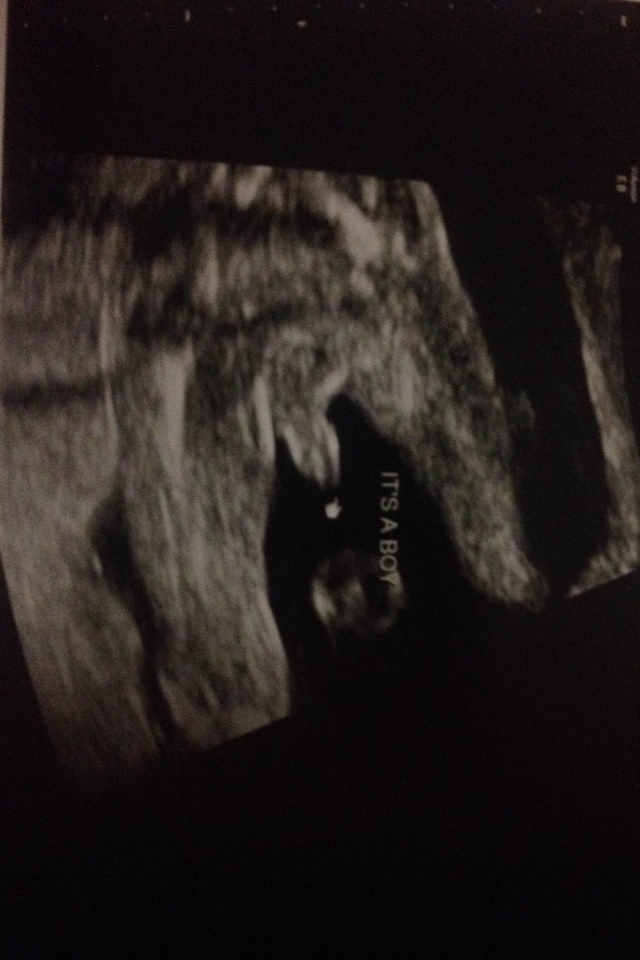

Attachment 20870 20 week ultrasound

Congrats on your baby!! he most certainly is a little boy! x